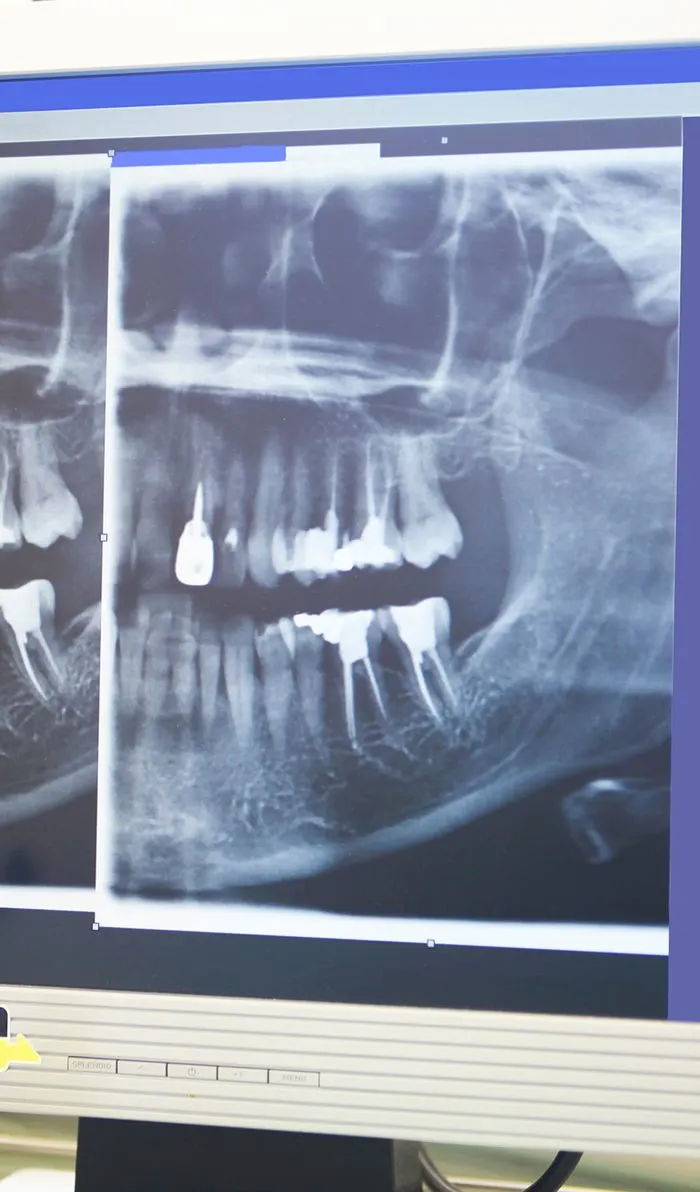

Diagnostics & Preparation

Your dentist will begin with a comprehensive examination of your tooth and x-rays to identify the cause of your dental discomfort. If an infection is present, they'll assess its severity to determine if a root canal is the appropriate treatment option.If root canal therapy is necessary, your dentist will ensure the treatment area is completely numb, including the nerves. Before starting the procedure, they'll discuss various sedation options with you to ensure your comfort throughout the treatment.